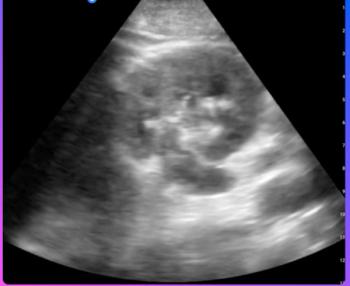

The result is spatial resolution close to that of CT and MRI,according to Sharbel Noujaim, global business leader for GE. Anearly uniform dot size produces texture that is the same virtuallythroughout the gray-scale image display in both the near- andfar-fields. Logiq 700 MR is capable of visualizing objects 300microns or less; its color flow is capable of visualizing downto 1 mm, and its real-time, pulsatile power Doppler is unlikeanything ever previously demonstrated at a scientific meeting,according to the vendor.

Goldberg presented cases demonstrating ultra-high resolutionin gray-scale and color Doppler on human and animal subjects.In one case the new technology showed the sutures that tied asurgically repaired carotid artery together; in a kidney and ina gallbladder, small structures were revealed with great easeand at great depths, Goldberg said. He noted the ability of Logiq700 MR to store and recall an image taken earlier for comparisonwith a current image, a feature that proved useful in comparingthe response of a pancreatic duct before and after chemical dilation.

Goldberg showed images from Logiq 700 MR compared with thoseof other high-end ultrasound equipment to demonstrate the comparativeclarity delivered by the GE scanner and the ability of the machineto find and delineate structures not otherwise seen. In one case,the system found lesions that were missed on an MRI study of apatient.

In applying color flow and power Doppler to renal, liver, andperitoneal animal studies, Logiq 700 MR delivered increased resolutionwhen contrast media were used.

"I don't see anything but a positive (result) when youget more resolution," Goldberg said. "We saw lesionsof high contrast down to 1 to 2 mm on animals that we could clearlydefine, whereas we had been talking about 5 mm before."